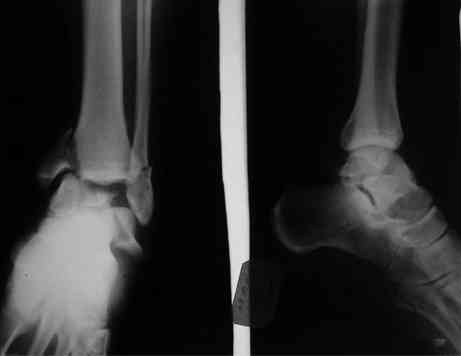

Interesting case

The ankle joint looks ruined. I wonder howcome is it as ruined after 2 days. I would open the joint( Some people would artroscope it) and judge the osteosynthes vs ankle fusion according to the ankle joint condition. The subtalar does not look injured, but if you feel there is a clinical

problem- CT it. Above all- when I see such an X-Ray I call the resident who ordered it and tell him that I would expect him first thing to reduce it on arrival since the soft tissue suffer and I hope that currently the p-nt is reduced to some extent at least.

Sorry- I revised it and the talus is fractured- take him to the theater at once and reduse it with Int Fix

The soft tissue will be a problem- Ex Fix will be better thn plaster

а основании двух видов ренгенограмм невозможно радикально решить о необходимости открытой репозиции или первичного артродеза.

И второй случай из недавней ташкентской практики, (извините за качество ренгенограммы и только в одной проекции) случай падения с высоты (кстати моего друга - известного киноактера) - открытый

смещенный перелом тарана, с переломом переднего края дистального эпиметафиза большеберцовой кости.

При поступлении в приемной сделана первичная обработка с ушиванием открытой латеральной раны и вытяжением за пятку.

повторили рентгенограммы и доделали проекции, к единому мнению все еще не пришли